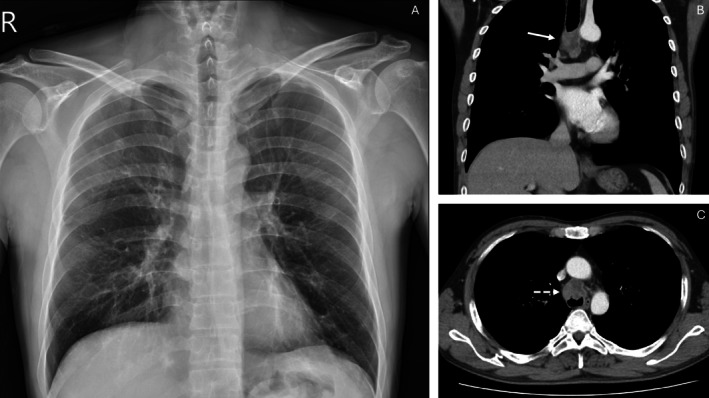

Tracheal tumours can develop as primary neoplasms or as extensions from adjacent organs such as the lungs or larynx. We present a case of a man diagnosed with adenoid cystic carcinoma of the trachea.

Abstract Image